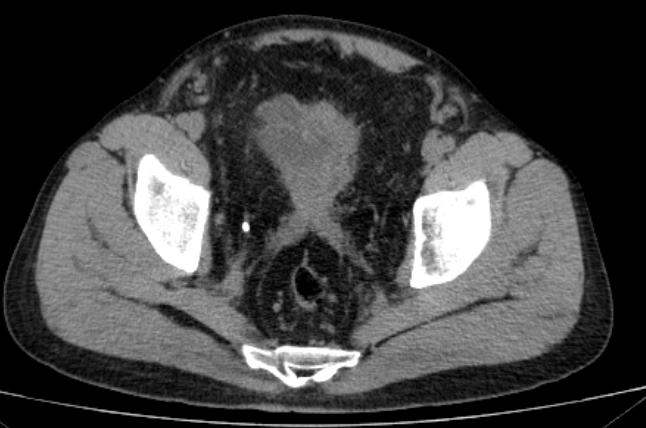

进一步完善泌尿系CT发现

患者除了双肾重度积水

输尿管扩张之外

盆腔有大量脂肪堆积

CT显示赵大哥双肾重度积水

盆腔脂肪明显增多,前列腺抬高,膀胱挤压变形